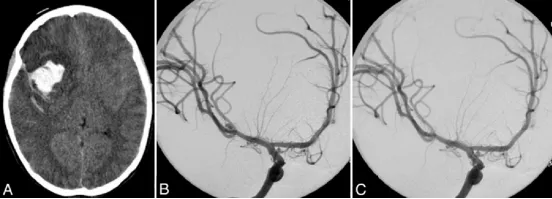

图1.A:非增强CT扫描,显示右额叶出血,侧裂内可见致密蛛网膜下腔出血。

B:右侧颈内动脉脑血管造影斜位片,显示一个5毫米大小的大脑中动脉(MCA)三分叉处动脉瘤。

C:右侧颈内动脉脑血管造影斜位片,显示MCA动脉瘤已成功实施血管内弹簧圈栓塞术